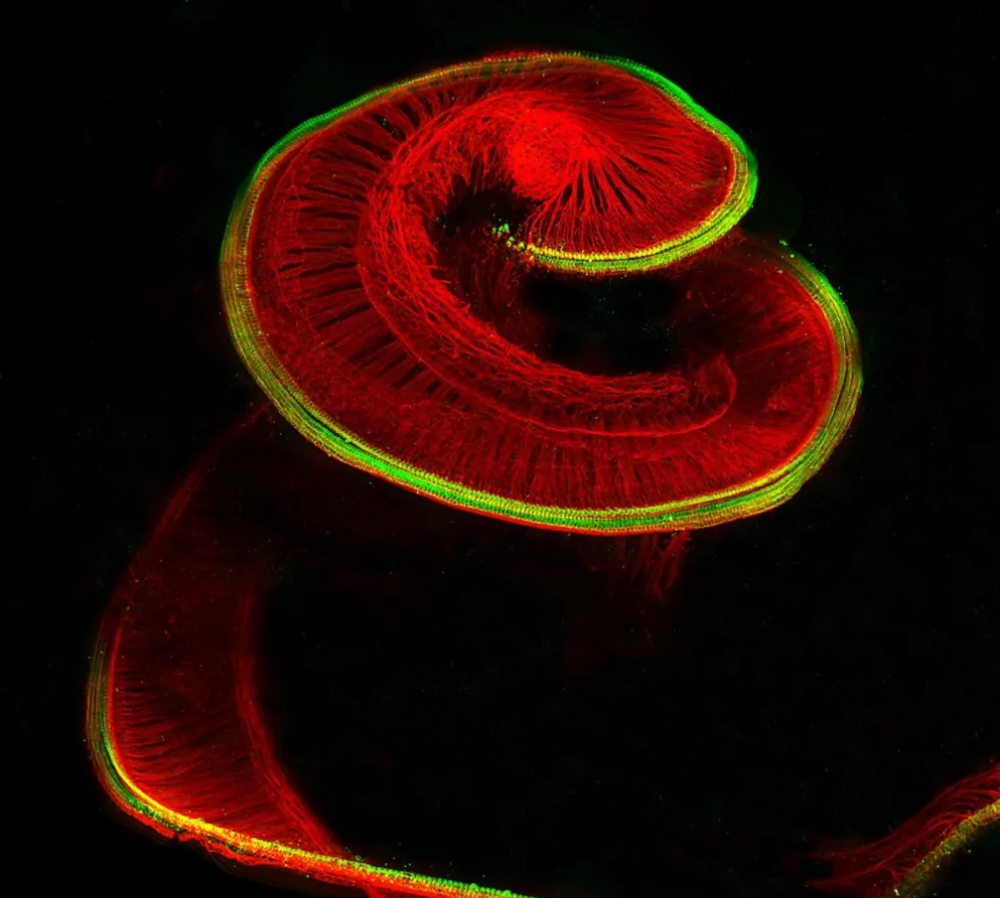

#8 Vnútorné ucho potkana

Kochlea zobrazuje vláskové bunky (červené) a neuróny (zelené). Táto štruktúra premieňa zvukové vlny na elektrické signály.